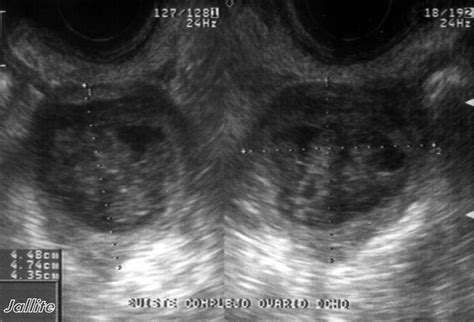

• Ultrasound: This imaging test uses sound waves to create images of the ovaries and can help determine the size, location, and type of cyst.

• quiste complejo de ovario